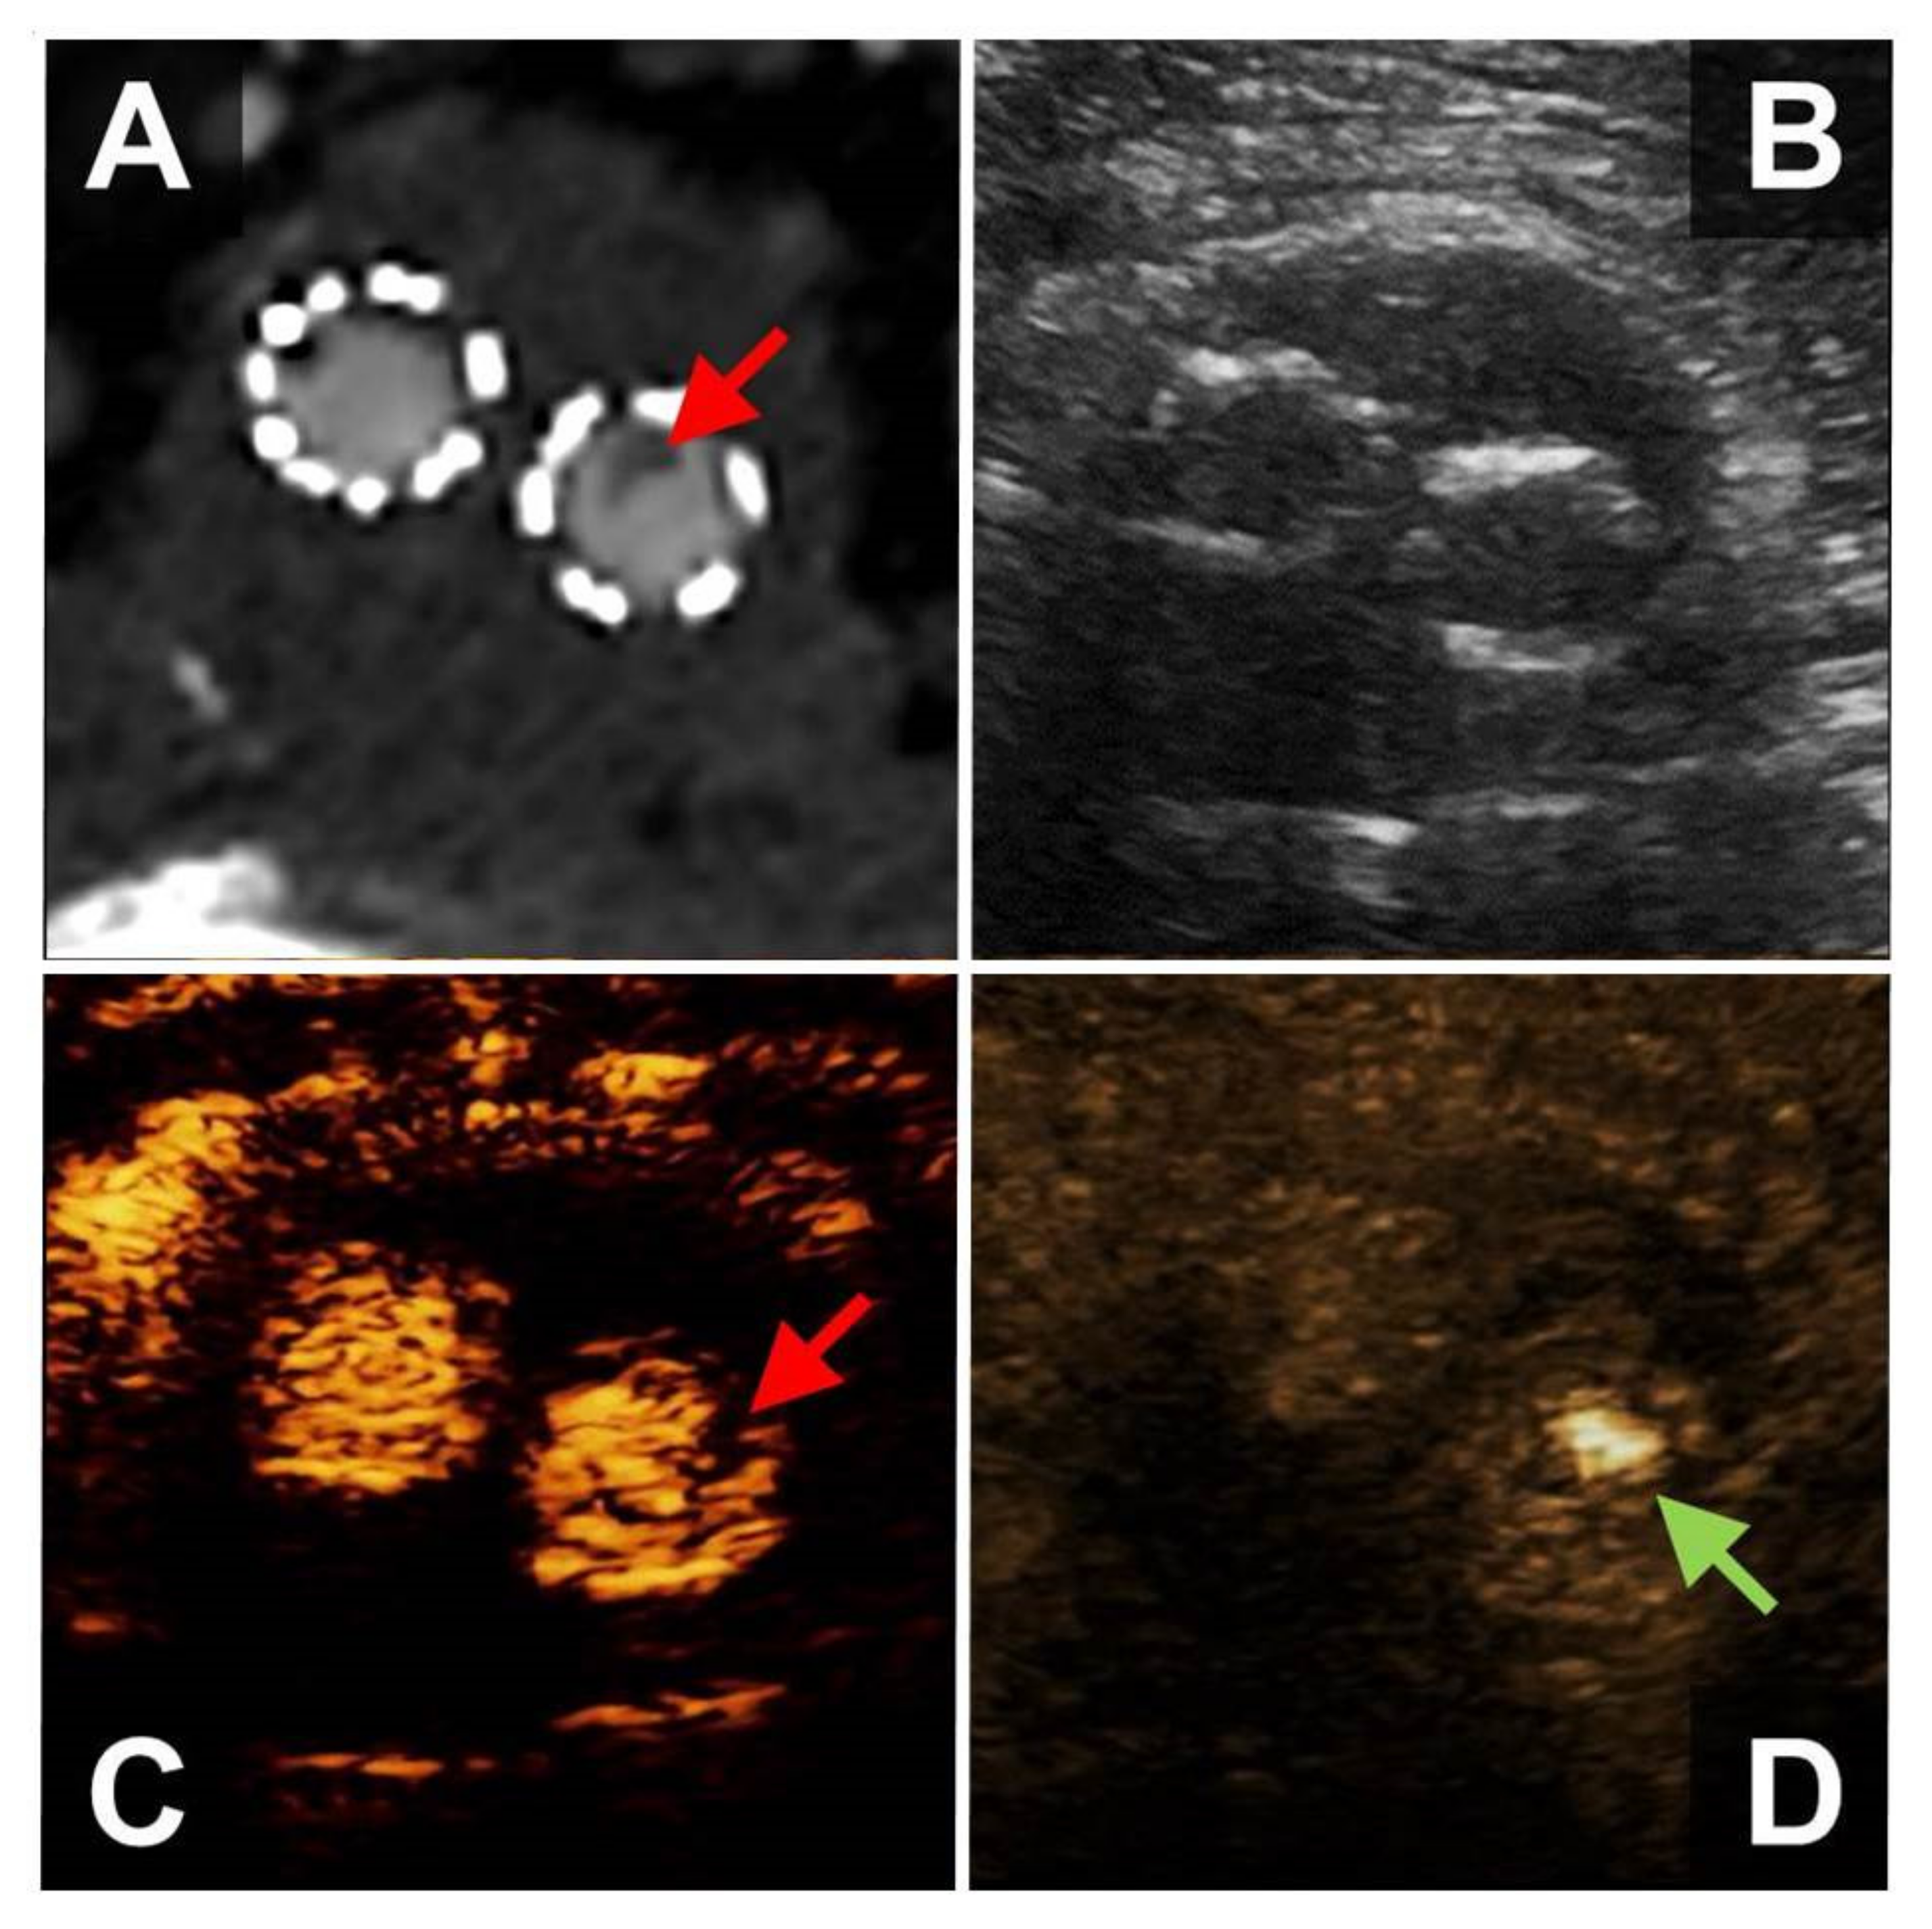

The FLS was found in 10 male patients who had undergone EVAR of an infrarenal abdominal aortic aneurysm, four of whom presented with embolic occlusions of the popliteal and/or below the knee arteries. In six patients, the FLS was detected during routine surveillance after EVAR (Figure 2, Video S2).

The FLS was detected in the right and left EVAR limb in four patients, respectively, and two patients exhibited the FLS in both EVAR limbs. All embolic occlusions were located ipsilaterally to the FLS (three patients with unilateral embolism, one patient with bilateral FLS who developed metachronous bilateral popliteal artery embolism). In another patient who underwent endovascular thrombectomy for right-sided embolic popliteal artery occlusion, the FLS of both EVAR limbs disappeared after four weeks of anticoagulation with low molecular weight heparin. After discontinuation of low molecular weight heparin, the patient suffered from embolic re-occlusion of the right popliteal artery, and a prominent FLS corresponding to a large floating intraluminal thrombus was detected in the right EVAR limb.

Nine patients also underwent CEUS-imaging, which detected intraluminal floating structures in six patients (66%). CTA was performed in eight patients and allowed for the detection of wall-adherent structures within the EVAR-prosthesis in seven cases.

Figure 2. 56-year-old male patient who underwent EVAR implantation for exclusion of an infrarenal abdominal aortic aneurysm. WAFAS (arrows) in the left limb of the EVAR prosthesis detectable by CTA (panel A), CEUS (panel C) and BFl (FLS, panel D), but not visible in B-mode sonography (panel B). EVAR, endovascular aortic repair; WAFAS, wall-adherent, floating arterial structure; CTA, computed tomography angiography; CEUS, contrast-enhanced ultrasound; BFl, B-Flow; FLS, flashlight sign.